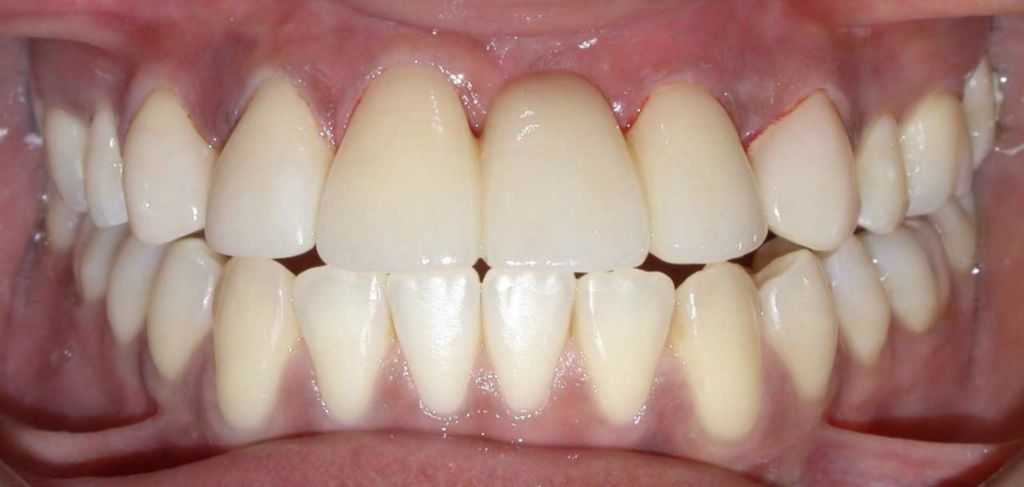

After

-